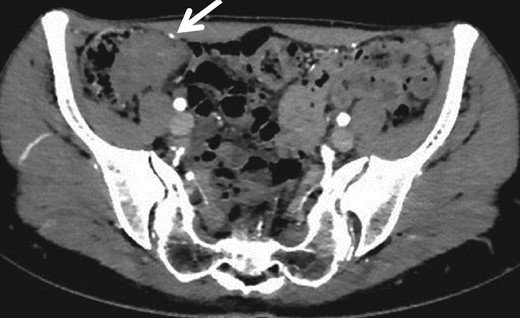

A 30-year-old woman underwent left ovariectomy and right ovarian endometrioma resection. At 40 years old, she noticed hematochezia and right-lower abdominal pain during menstruation, the symptoms continued over 3 years. At 43 years old, although she no longer noticed the same symptoms, she had right-side chest and back pain during menstruation so visited the doctor. A tumor of the ileocecum and right pneumothorax were discovered by computed tomography (CT). Pneumothorax was improved by conservative treatment. Submucosal tumor (SMT) was discovered at the rectosigmoid (RS) by colonoscopy (CS). The patient was referred to our hospital. A 3 cm size mass was discovered in the right-lower abdomen. Rectal examination was unremarkable and laboratory data was normal. CS showed the SMT with erosion at RS (Fig. 1a). As the scope could not pass through the sigmoid colon, we used the double balloon endoscopy. We observed erythrogenic mucosa of the ileum resembling salmon roe (Fig. 1b), and the cecum was suppressed from the outside. Biopsy was taken from the RS and ileum, but the pathological result was benign. Endoscopic ultrasound guided fine needle aspiration was also performed from the RS, but no abnormal cell were observed. By abdominal CT, a mass lesion was recognized at the ileocecum. No abnormal lesions were recognized at the rectum (Fig. 2).